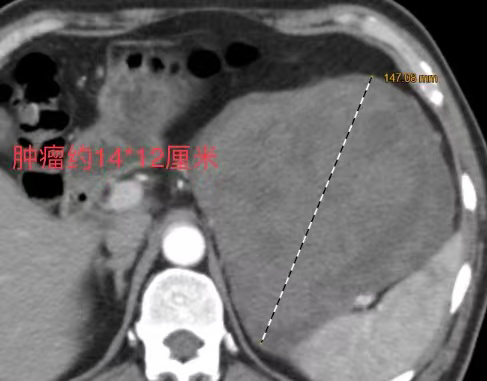

患者病情初步稳定后,查明出血根源成为彻底治愈的关键。进一步检查证实,此次险情的“元凶”是一枚直径约15cm的胃巨大肿瘤——该肿瘤包绕脾脏血管、压迫胰腺,如何在手术中保留脾脏和胰腺是一大难题,手术难度系数极高。